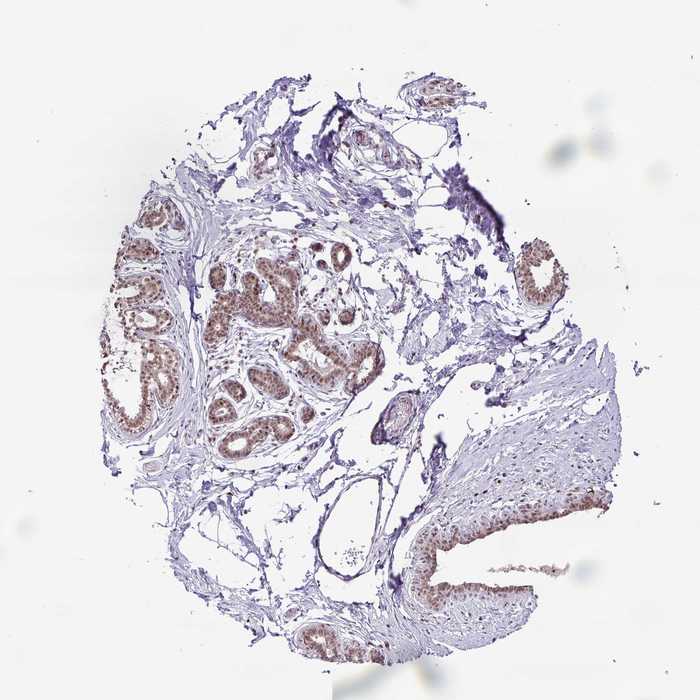

BREAST - Antibody stainingi

Antibody staining in the annotated cell types in the current human tissue is reported as not detected, low, medium, or high, based on conventional immunohistochemistry profiling in selected tissues. This score is based on the combination of the staining intensity and fraction of stained cells.

Each image is clickable and will lead to virtual microscopy that enables deeper exploration of all samples and also displays staining intensity scores, fraction scores and subcellular localization as well as patient and tissue information for each sample.

Antibody HPA051830

Adipocytes Not detected

Glandular cells Medium

Myoepithelial cells Medium